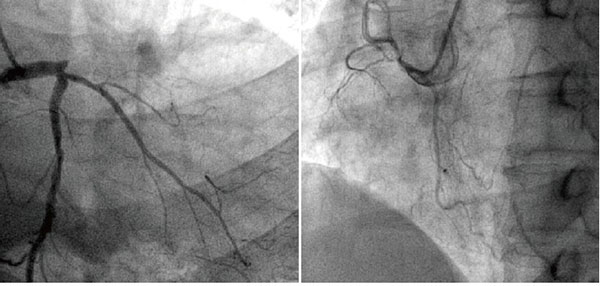

冠脈造影

冠狀動脈是給心臟供血的血管,當(dāng)這個血管或者它的分支出現(xiàn)病變,我們就會患上冠心病(心肌缺血)。在輕度病變的時候, 患者沒有癥狀,或者出現(xiàn)心絞痛。嚴(yán)重病變的時候會有形成心肌梗死的風(fēng)險。

前臨床常用的冠狀動脈造影檢查包括冠狀動脈CT血管造影(CTA)和介入冠狀動脈造影兩種,都是評價動脈是否存在病變以及指導(dǎo)治療的重要手段,兩者各有優(yōu)缺點,也各有利弊,在不同情況下選擇不同的檢查方式,需要根據(jù)情況來決定,不能一成不變的認(rèn)為CTA好或者介入造影更好。